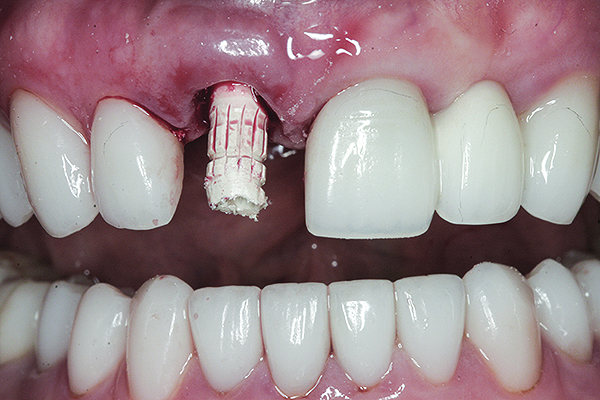

The master cast and abutment were returned to the laboratory for fabrication of the restoration (Figure 15). An all-ceramic crown (e.max®, Ivoclar Vivadent) was fabricated on the custom abutment; it matched the contours of the adjacent central incisor. After completion of custom shading, the definitive abutment and crown were returned to the restorative dentist. The abutment was tried in (Figure 16), and a radiograph was taken to confirm complete seating between the abutment/implant and the crown/abutment. The definitive abutment screw was torqued to 20 Ncm, and the screw-access opening was blocked out with Teflon tape.

Fig 16. Try-in of the definitive titanium-nitride–coated abutment.

Figure 16